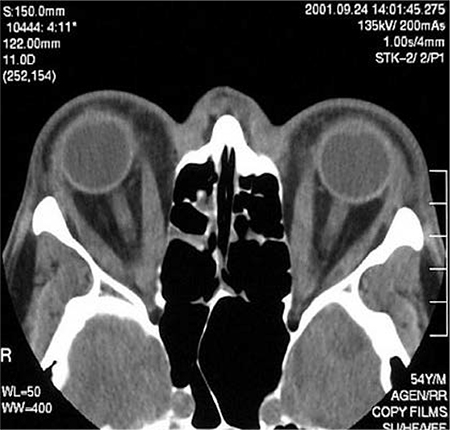

TC axial através das órbitas de um paciente com orbitopatia de Graves exibindo espessamento elevado dos retos mediais

Cortesia do Dr. Petros Perros